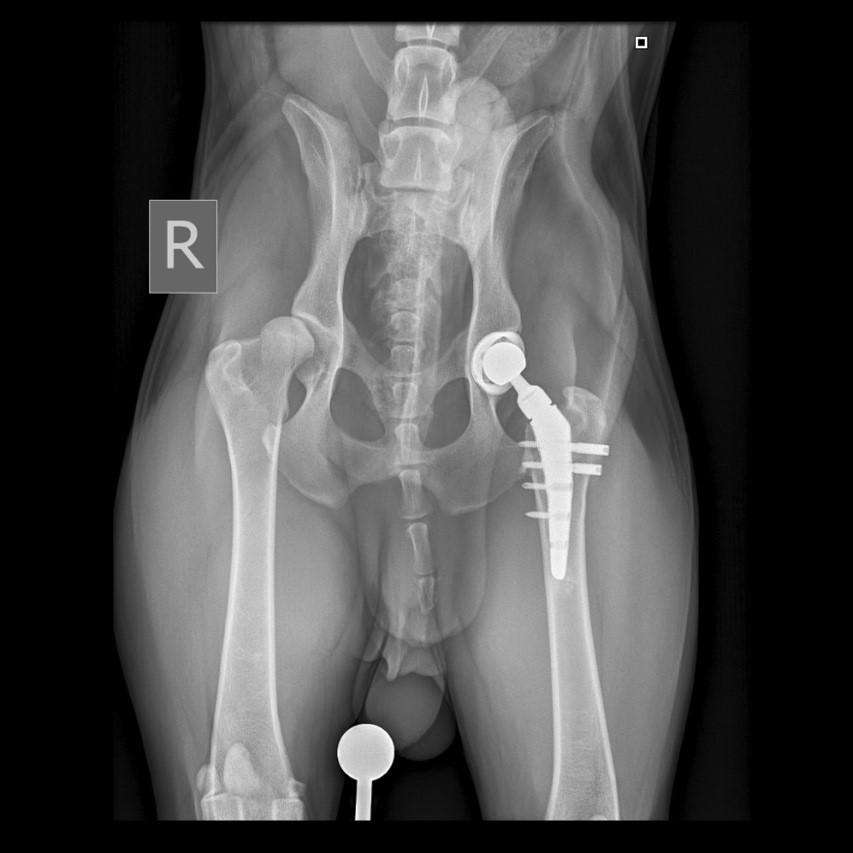

Было рекомендовано и проведено хирургическое лечение – протезирование тазобедренных суставов с интервалом между операциями в 3 месяца (фото 4).

После завершения операции выполняется серия контрольных рентгенограмм для оценки положения имплантатов (фото 4, 5).

При остеоартрите объективным доказательством наличия хронической боли может служить снижение мышечной массы больной конечности (фото 4). При односторонних состояниях это можно проверить посредством ее сравнения с мышечной массой здоровой конечности. В билатеральных случаях, например при дисплазии тазобедренных суставов, наблюдается общее снижение мышечного тонуса в мышцах тазовых конечностей6.